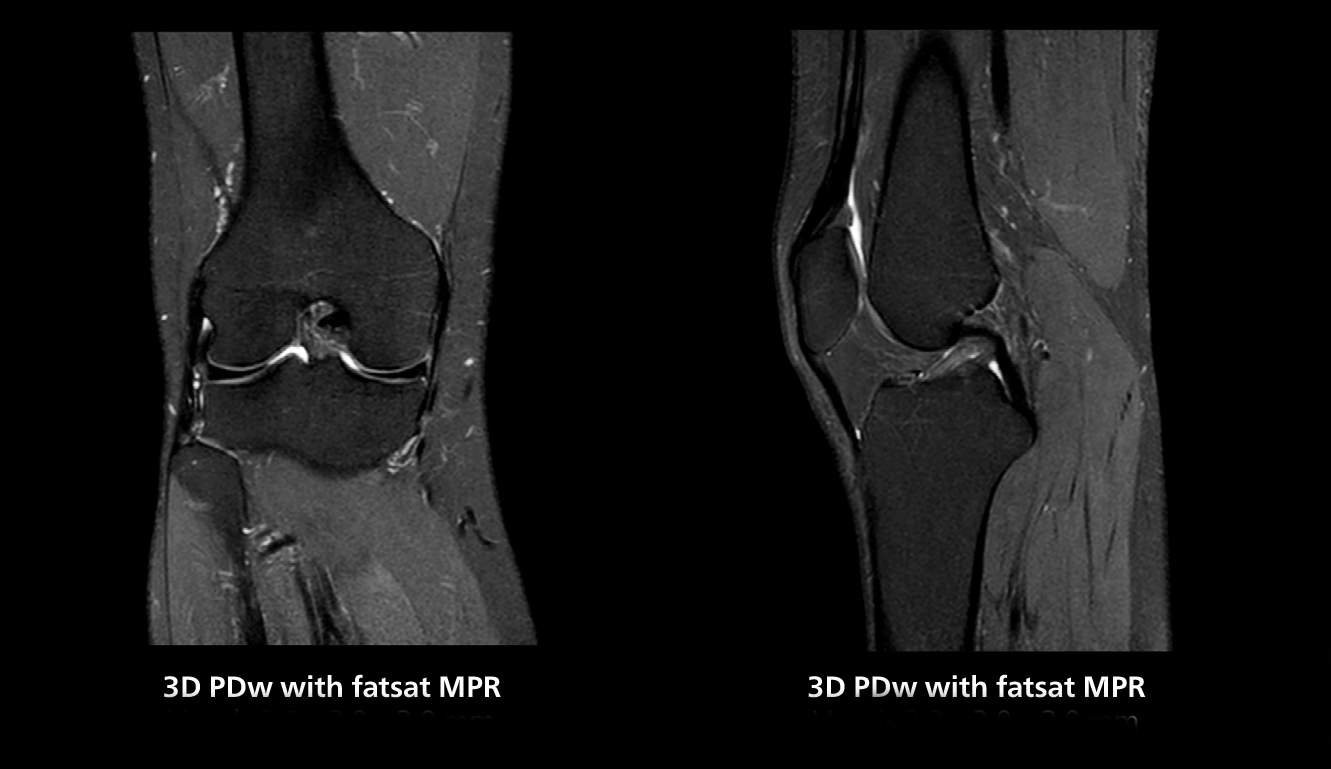

3D knee imaging

The isotropic high resolution 3D sequence in this MRI case allows for reformatting to obtain other orientations with high quality. Acquired on the MR 5300 system.

According to Dr. Gellée, the hospital conducts an average of four studies each hour, totaling about 40-45 patients per day on their MR 5300. Studies are read by approximately 50 radiologists in the Bordeaux area. Dr. Gellée is especially satisfied with the image quality of the MR system. "I obtain higher image contrast and more anatomical precision than I was used to,” she says. “When I am able to choose, I request that studies be done on this system, because I get better anatomical image quality. For example, in the knees, I can get great images of the meniscus. To me, it looks as pretty as 3T.”